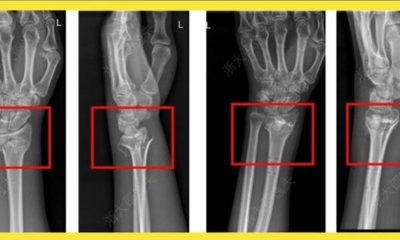

Em caso experimental, um paciente com fratura no punho recebeu uma injeção através de uma incisão de apenas 3 cm e foi curado em apenas três...